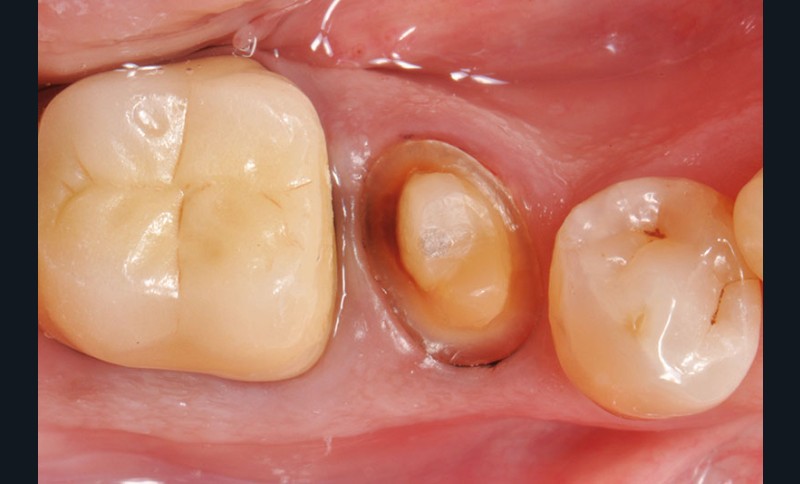

6. Après réalisation de la préparation périphérique externe, la hauteur, la largeur et l’épaisseur des parois résiduelles sont évaluées, ce qui permet de poser l’indication d’une RMIPP (reconstitution par matériaux insérés en phase plastique).